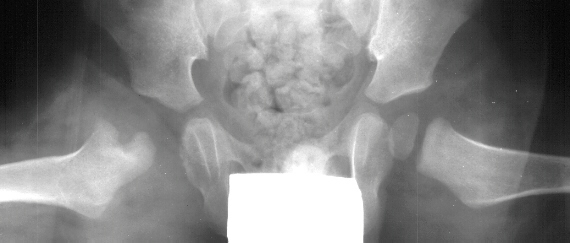

- Post Operative Day 18: R hip Xray: subluxation of R hip, possible metaphyseal

lucency consistent with osteomyelitis. Taken to OR for repeat I & D

Institute. Initial labs: WBC 15,100, ESR 72. R hip Xray: changes in proximal

. metaphysis including lucency and demineralization, hip subluxated. Treated

with oxacillin and Pavlik harness.

- 2 month Office Follow Up: Rt hip Xray: progressive destruction of capital

femoral epiphysis, cystic changes in metaphysis consistent with AVN.

This case is an example of untreated septic arthritis which caused avascular

necrosis of the proximal femur. The primary cause of this is undrained

septic hip. Repeated aspiration is not adequect treatment of a septic hip.